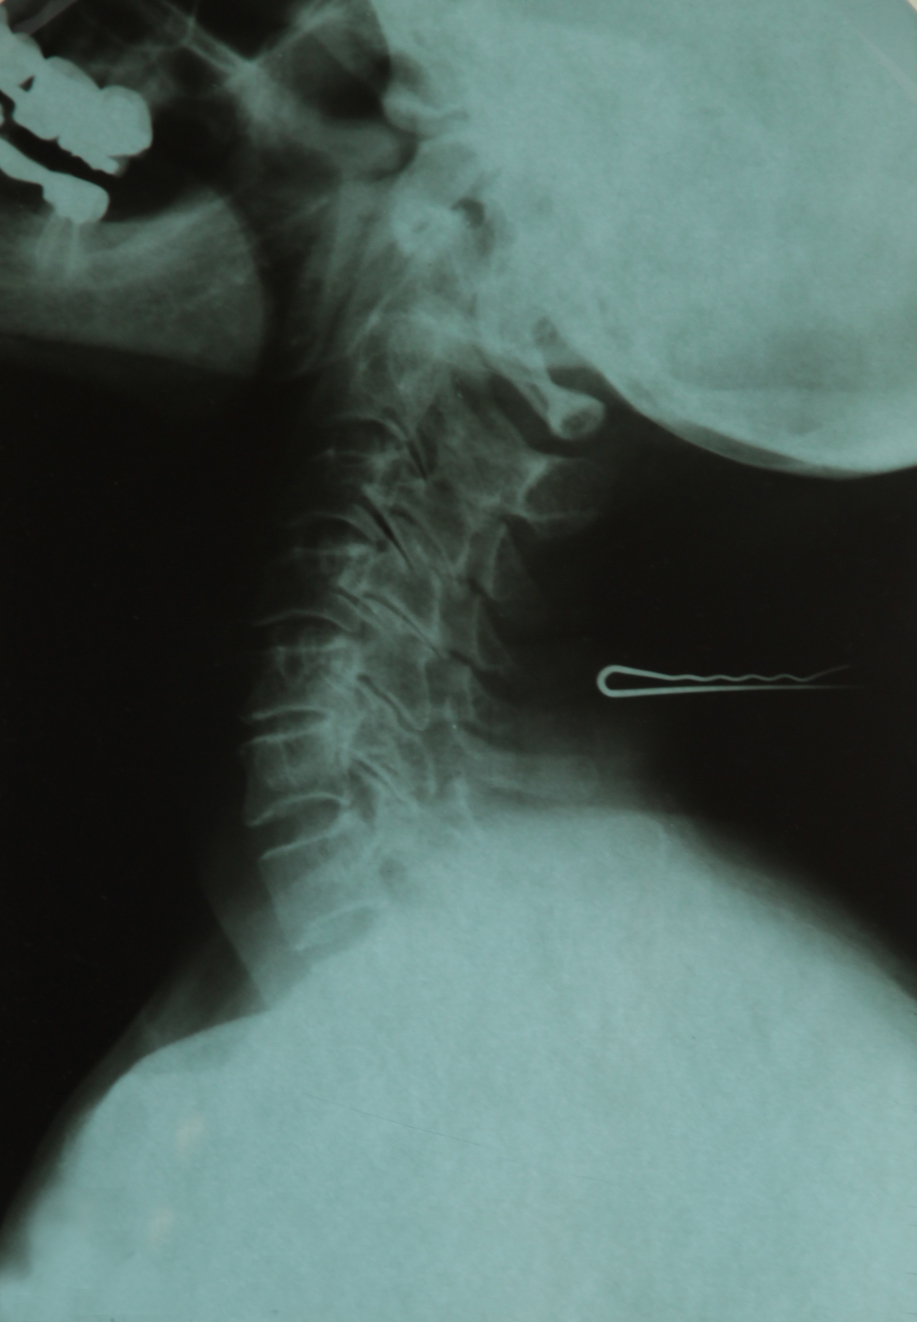

X-RAY. A Family Album (Serie aus 5 Röntgenbildern)

Shahram Khosravi konstatiert zur gesellschaftlichen Bedeutung des Röntgenblicks in seinem Essay „Strahlen der Gewalt“: „Der medizinische Blick des Röntgenapparates funktioniert als biopolitisches Instrument, das Körper im Rahmen der Altersbestimmung von Asylsuchenden, des Visumantrags von Migrant:innen, der Kommerzialisierung von Frauen und der Kriminalisierung von Minenarbeitern reguliert und diszipliniert. Dient die Röntgentechnik einerseits der Rettung von Leben, ist sie andererseits Hilfsmittel von Kontrolle und Unterdrückung.“